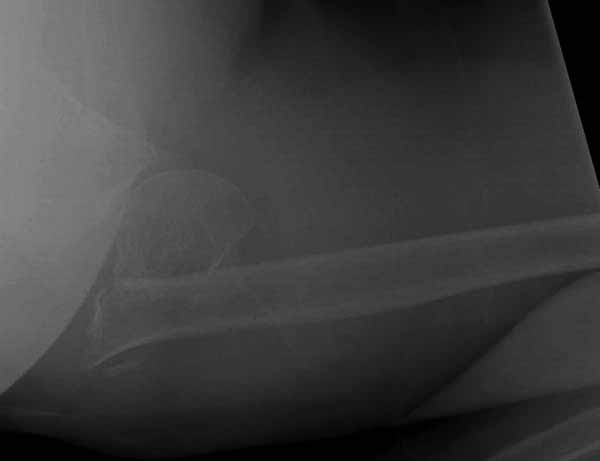

Уважаемы коллеги! Прошу помочь определиться с тактикой лечения пациентки. В феврале в отделение поступила пациентка с оскольчатым переломо-вывихом головки плечевой кости. Выполнена операция -остеосинтез блокируемой пластиной. Костная пластика не производилась. На контрольных рентгенограммах остается сублюксация головки и смещение большого бугорка. Интраоперационно бугорок подшивался с помощью лавсановых нитей. Послеоперационно: ношение косыночной повязки и пассивные движения в плечевом суставе в течение 2,5-х месяцев без особенностей. Через 2,5 месяца при попытке выполнения пассивно-активных движений произошел передний вывих плечевой кости.Вся реабилитация производилась по месту жительства. Таким образом существование вывиха в течение 1 месяца. Боли не беспокоят. Нейрососудистых нарушений в конечности нет. Что вы можете посоветовать: пластику, эндопротез, артродез? Заранее спасибо.

Набор мелких снимков не отражает истинную картину суставной поверхности лопатки, а также качество репозиции головки плеча. Необходимо доказать аксиальным снимком наличие покрытия головки. Правильная маркировка на рентген снимках и соответствие с выставленным диагнозом гарантирует от ошибок со стороной во время операции!